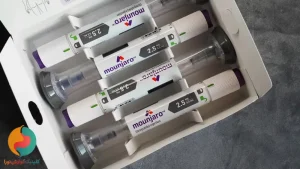

کلینیک بوتاکس معده

درباره بوتاکس معده بیشتر بدانیم

بوتاکس معده تزریق سم بوتولینوم به دیواره معده است. و باعث می شود عضلات دیواره معده به طور موقت شل بشود.

بوتاکس معده به روش غیرجراحی و از طریق آندوسکپی انجام می شود. اسکوپ را از طریق دهان وارد معده می کنند و با سوزن داخل اسکوپ بوتاکس را به دیواره معده تزریق می کنند.

نمونه هایی از عمل جراحی بوتاکس معده توسط دکتر رضادوست برای بیماران داخلی و خارجی

بوتاکس معده یکی از جدید ترین روش های کاهش وزن است که با استفاده از اندوسکوپی انجام می شود، ابتدا معده از نظر وجود ضایعاتی از جمله:پولیپ، زخم یا التهاب بررسی می شود.

این روش بدون بیهوشی و بدون جراحی انجام می شود پزشک از طریق لوله آندوسکوپی، دارو بوتولونیم (بوتاکس) را از مری وارد معده و به ۳۰ تا ۴۰ نقطه از معده که از قبل تعیین شده تزریق میکند، دارو بوتولونیم به مدت ۴ الی ۶ ماه (بستگی به متابولیسم بدن شما دارد) ماهیچه های دیواره معده را بیحرکت کرده و از انقباض آنها جلوگیری می کند. فرایند تزریق بوتاکس به معده حدودا ۲۰ دقیقه زمان می برد.